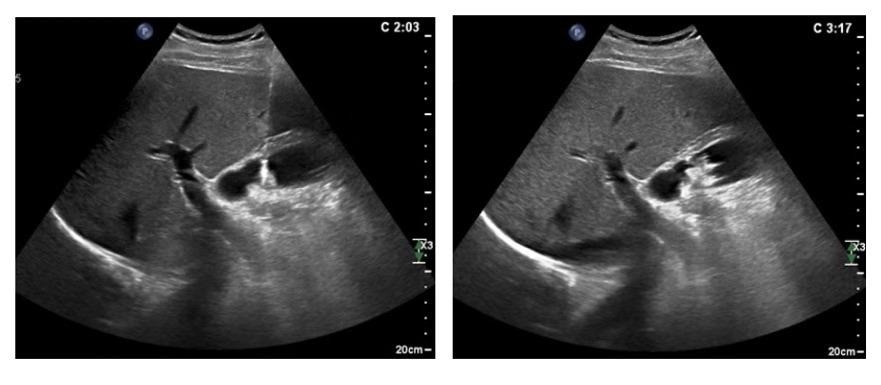

术后患者未出现胆囊穿孔、出血等明显并发症,精神状态良好。观察一天后给予超声造影检查:

可见占位未见强化,已完全“灭活”,胆囊壁水肿消失,恢复了正常厚度,胆囊壁未受明显损伤。次日活检病理提示:胆囊幽门腺腺瘤。